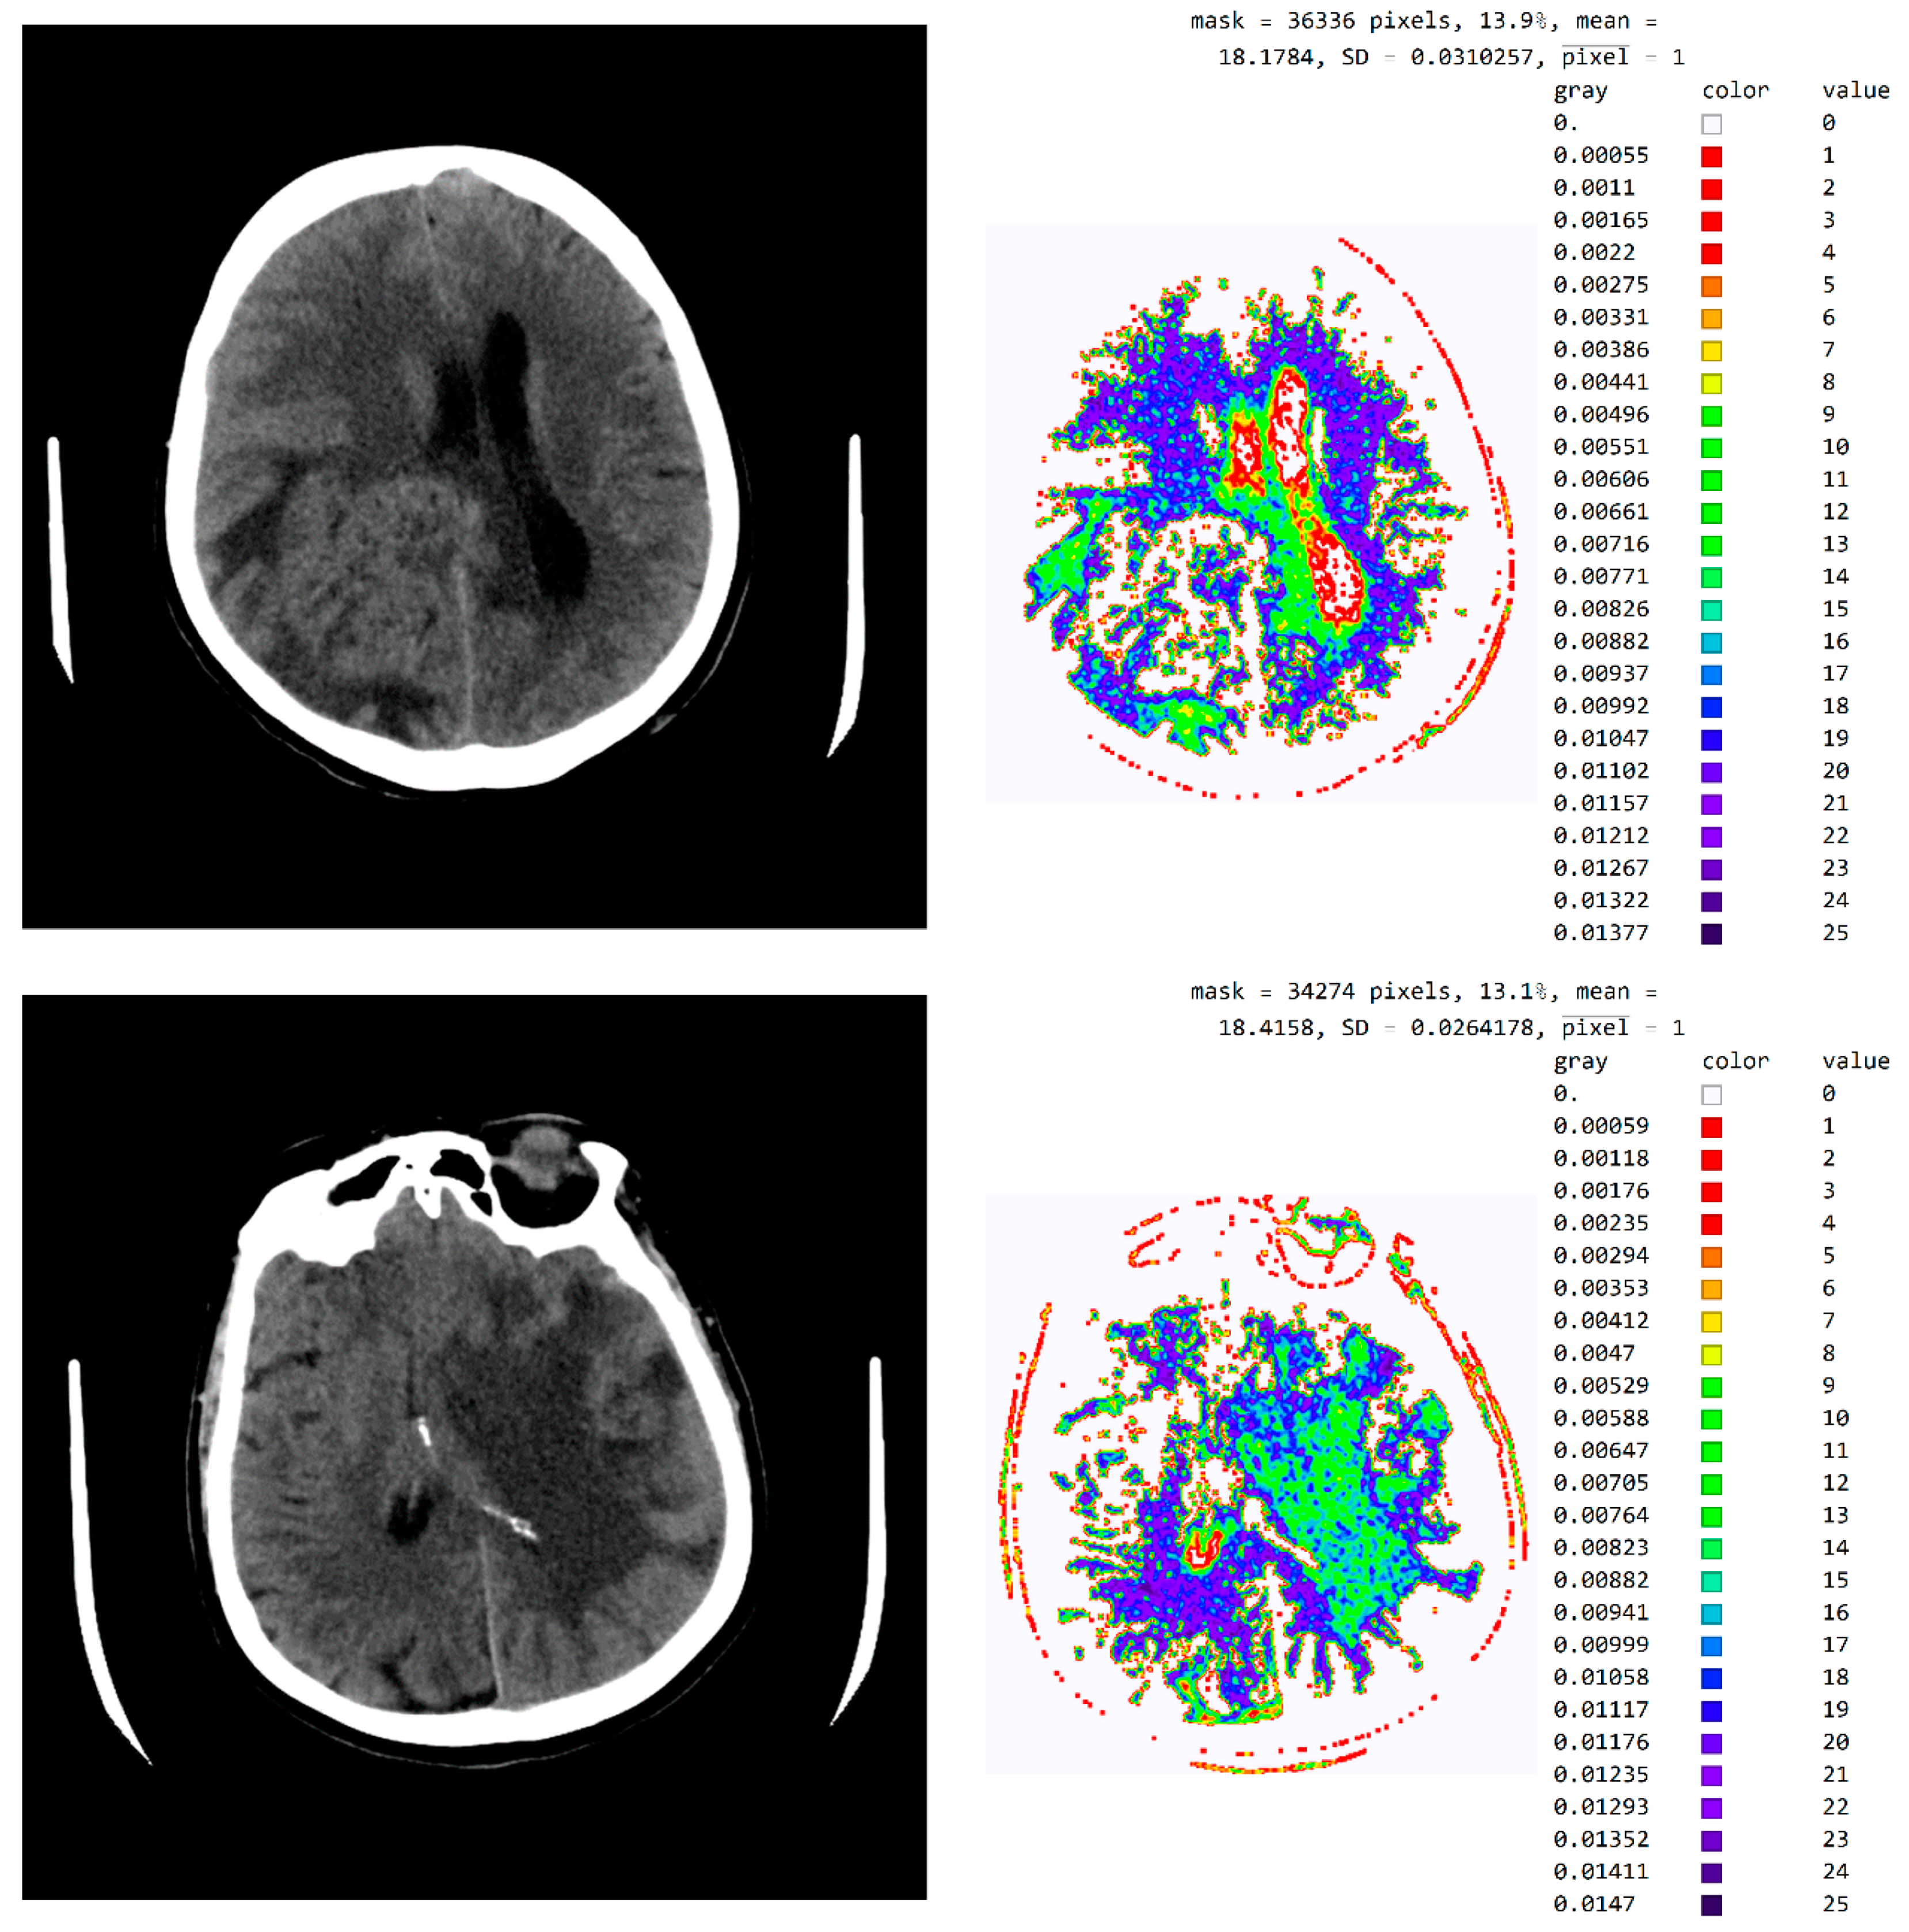

This chapter presents a technological description of the developed SVMI model, which describes image processing according to the proposed method. The image used in the survey questionnaire to evaluate the developed SVMI model was selected for its illustration and technological description. The primary characteristics of the selected image are that it has 512 × 512 pixels or a total of 262,144 pixels of integer-type. Pixel values remain unchanged when the image format converts. The analyzed image in PNG format has the same pixel values as the original image, so the image has no losses after processing. However, many pixels do not contain valuable information, and the first task of the software is to eliminate all pixels from the image that may be misinterpreted or confusing. For the analyzed image, for example, the number of pixels with zero values were calculated. Out of 262,144 pixels, as many as 158,881 pixels had a value of zero. Useful pixels with small values (for example, 1, 2, 3 ...) are difficult to distinguish from values of zero, so it was necessary to eliminate these pixels before analysis by an expert. The number of pixels as a function of value is shown in Figure 4.

Figure 4.

The number of pixels as a function of value.

Figure 4 shows a large number of pixels with values between 10 and 100 and 22,331 pixels have a value greater than 100, while the most considerable value of pixels is 1682. Some programs can automatically adjust the image display to highlight pixels that improve the display of a portion of the image. For example, to increase the contrast or brightness of a portion of an image with a large number of pixels., image adjustment can be used to adjust pixel values so that more of the image content is in the visible range or to correct lousy illumination or contrast. The purpose of this software is not to distort the image display without a specialist’s control, but to accurately display the part of the image that contains valuable information on a linear scale and remove pixels from the image that do not valuably contribute to the image content. Pixels with an immense value make it impossible to display valid pixels on a linear scale from zero to one and increase the average value of helpful information pixels. One way to remove un-useful pixels from an image (Figure 5a) is to set high-value pixels to zero (Figure 5b) and to generate a pixel mask, shown in black in Figure 5c.

One can now look at what a histogram of pixel values greater than zero and less than one hundred looks like, as is shown in Figure 6b, which demonstrates what the display range for visual analysis by a specialist can be for an image whose values will be in the range from 5 to 55, i.e., that the upper threshold for the pixel value does not need to be 100. To more clearly identify the pixel values, we have chosen to display 24 different levels in which the expert can choose which range they want to observe. All other values are associated with a mask that appears to be zero, and these values are not counted as the mean value.

Figure 7 shows a histogram for 24 successive levels from the range {18, 42}, for which a mean value of 30 was calculated. Based on the histogram in Figure 7, the specialist can select the range of pixel values they wish to observe by masking all other values by setting them to 0.

In Figure 8, it can be seen that the third image (Figure 8c), comprising the central part of the circular image, contains 37.4% of the total number of pixels; that the second image (Figure 8b), comprising values from the pixel range from 1 to 55, contains 30.5% of the total number of pixels; and that the mask (Figure 8a) for the selected range of 24 successive pixel values contains 22.6% of the total number of pixels. By choosing the range of pixel values, the specialist can more easily identify the pixel values of interest to conclude the type of disease.

Figure 9 shows an image with exact integer values with shades of gray scaled from black (pixel value 18) to white (pixel value 42), with all other pixels outside this range shown as 0 (white in the picture). The far-right column contains the exact pixel values where it can be observed that the differences of adjacent values are scaled from 0 to a maximum of 1682 on the gray range from 0 to 1, approximately 1/1682 ≈ 0.0006, which makes it impossible to accurately determine the differential values in the original image without using algorithms to highlight a range of values. In addition to displaying pixels whose values are 18 to 42, image rescaling was performed, eliminating the display of parts of the image outside the mask of the circular segment that do not include valuable information. Since the specialist chooses the range of pixel values, Figure 9 clearly shows white parts that are not displayed but could contain valuable information. The specialist may choose a different range if they wish to see pixels from the pixel range of 1 to 55 and consider those pixels to be useful in diagnosing the disease.

The three Figure 10a–c show black pixel masks that will set all image values to zero so that white pixels can be displayed in the image. This mask has an additional setting of zero for all pixels in the upper third (near the eyes). The new mask allows for the display of 29.6% of the total number of pixels (Figure 10c); the mask with values outside the pixel range from 1 to 55 contains 25% of the pixels (Figure 10b); and the selected range of display contains 21.1% of the total number of pixels (Figure 10a).

The software also allows pixels to be displayed in color to help identify pixel values in an image. For example, in Figure 11, a color map based on light whose wavelength is in the most commonly used range in radiology (i.e., colors based on light wavelength in nanometers, Physics-Oriented Color Schemes) was selected. The color map may be different depending on what the specialist wants to emphasize to differentiate the values of adjacent pixels. In Figure 11, the minimum value was moved to 25 and not 18 because the specialist expected to see where the pixel values greater than 25 are. It is noted that a small number of pixels have a value greater than 40 and that they do not contribute to the recognition of the disease. Therefore, the specialist can choose a narrower range of values to display. High resolution between adjacent levels can negatively affect disease recognition, so it is desirable to perform averaging so that each pixel receives the average of several adjacent pixels in the image.

In Figure 12, the mean value of seven adjacent pixels was calculated and averaged from 25 to 50 pixels for the display range. Figure 12 was used in an online questionnaire to evaluate the developed SVMI model. The results showed that, in the practical education of MDs in the radiology residency training program, a decision on diagnosis was made in which 95% of the surveyed physicians made the correct diagnosis after SVMI processing and this diagnosis was confirmed followings additional diagnostics.